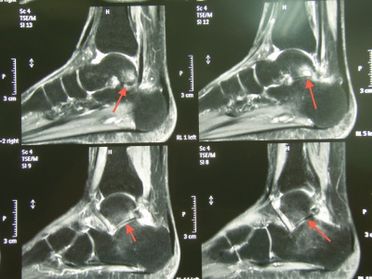

Fall 1

Links: In der MRT sieht man schwere Knorpelzerstörungen und Arthrosezeichen im unteren Sprunggelenk (Pfeile).

Rechts:

Nach Fusion und Verschraubung des unteren Sprunggelenkes geht die Patientin gut und schmerzfrei.